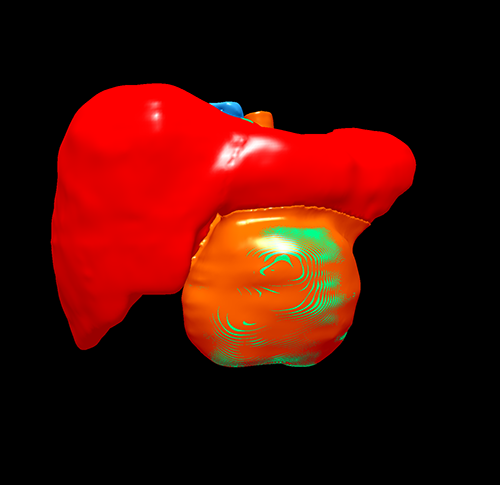

肝血管瘤--左肝外侧叶切除